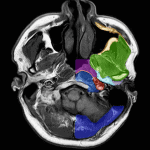

Giải Phẫu CT & MRI Vùng Cổ | Bài giảng CĐHA

Hình ảnh giải phẫu Cắt lớp vi tính / Cộng hưởng từ vùng cổ.